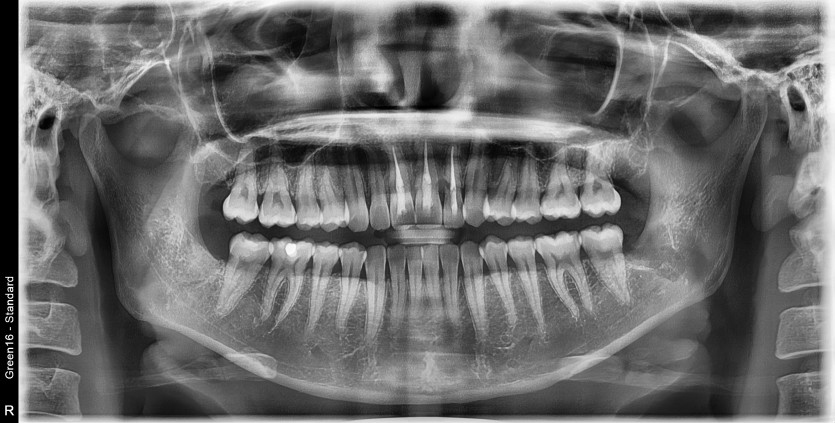

#28,38 사랑니 발치

구강 외과 전문의가 당일 발치했습니다.